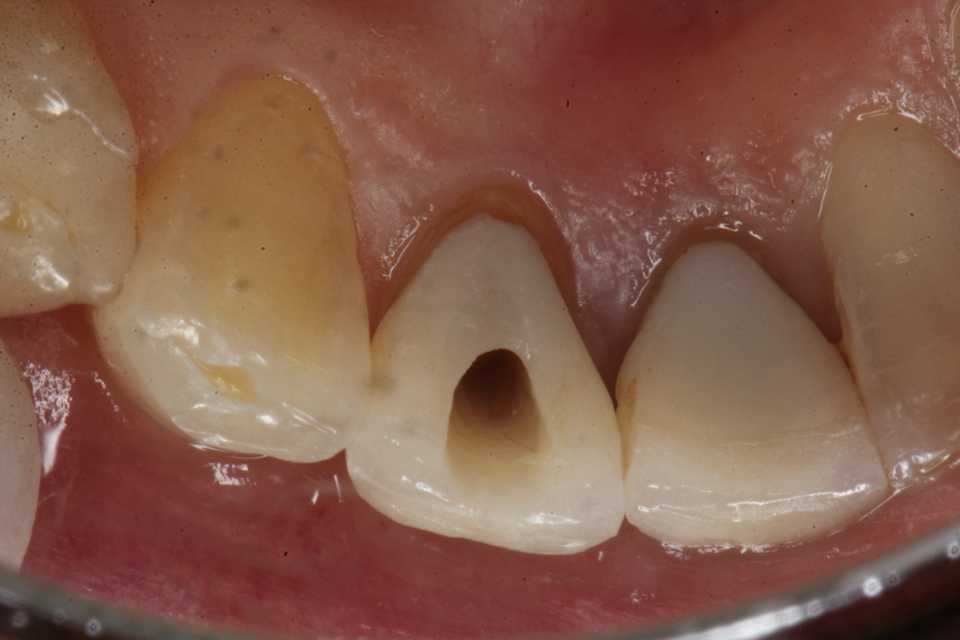

50代女性、左下1、Per(根尖性歯周炎)、GA(歯肉膿瘍)有り

治療前

根尖付近が腫れている。(実像)

舌側からアクセスする(鏡像)